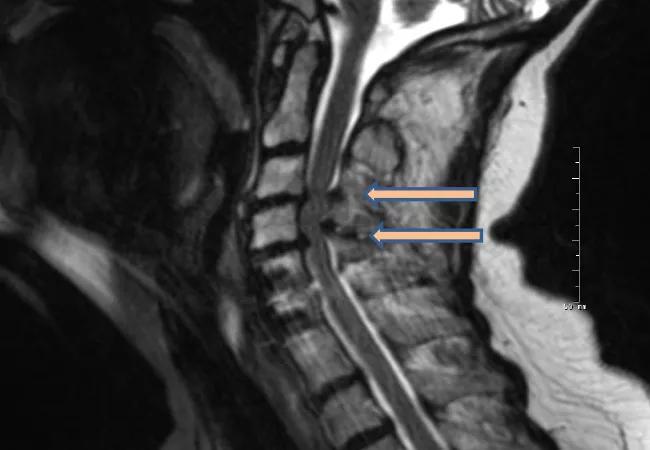

imaging study showing cervical spondylotic myelopathy in the neck

One year after surgery for cervical spondylotic myelopathy, patients report similar improvement in physical and general health measures regardless of whether they underwent a ventral or dorsal surgical approach. That’s the primary finding of the multicenter randomized Cervical Spondylotic Myelopathy Surgical (CSM-S) trial, believed to be the first randomized study to compare alternative surgical approaches for this common condition. Results of the trial were published in the Journal of the American Medical Association (2021;325:942-951).